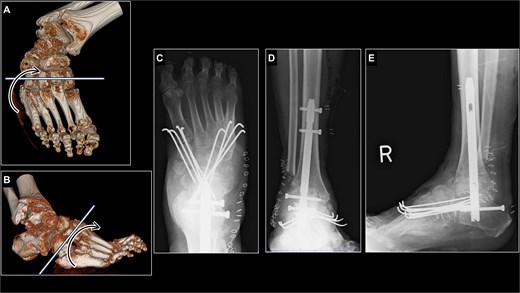

The surgery was performed in three steps. First, after removal of osteophytes and decortication of the joint surfaces as part of joint preparation for arthrodesis, Achilles tendon lengthening with gastrocnemius recession [11] was performed, allowing correction of the ankle to neutral dorsiflexion. Second, ankle and subtalar arthrodesis was achieved using a retrograde intramedullary nail (Ankle Phoenix Nail®, Zimmer Biomet, Warsaw, IN, USA) through a lateral approach. Although hindfoot correction was obtained, the rigid midfoot inversion persisted. Third, a midfoot derotational osteotomy was performed from the first cuneiform to the cuboid, dividing the bone into proximal and distal segments (Fig. 4A and B). The midfoot was manually derotated to correct the inversion, achieving plantigrade. Then, the osteotomy site was fixed with percutaneous 2.0-mm Kirschner wires inserted from distal to proximal (Fig. 4C–E), while carefully avoiding injury to the dorsalis pedis artery.

Surgical planning and postoperative radiographs of the right foot just after surgery. (A, B) an osteotomy line was established from the first cuneiform to the cuboid. (C) Midfoot derotational osteotomy site was fixed with eight K-wires. (D, E) Hindfoot was fixed with retrograde intramedullary nail while varus and equinus deformity was corrected.